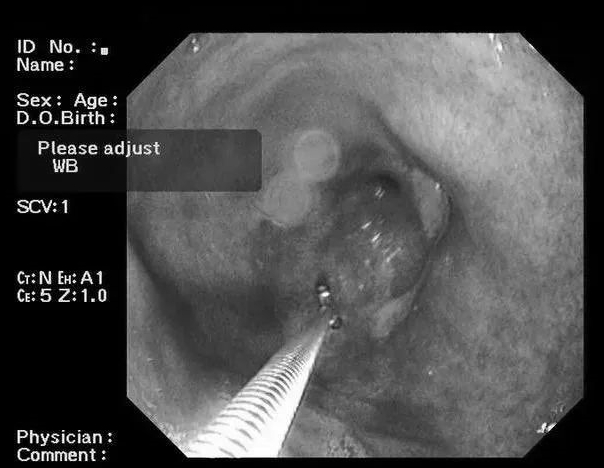

结果报告为:胃体2*3cm溃疡性病变(性质待定)。

于是在2020年6月重新做了胃镜,并取了活检。病理报告为:低分化印戒细胞癌。

胃镜虽然是发现早期胃癌的金标准,也并非100%不会漏诊,为了防止漏诊、误诊,一般都会建议,对于可疑病灶,要取活检做病理分析。

就是做胃镜的时候,在病灶上咬下一小块肉,送到病理医生那里,进行切片、染色,在高倍电镜下观察,对病灶的性质判定会非常准确,所以我们常说“病理医生是医生的医生”。

大约2%的胃溃疡可能发生癌变,在癌变早期尚未形成明显肿块等典型特征时,往往仅有溃疡边缘黏膜颜色的轻微改变,如果此时对溃疡周围的胃黏膜做病理检查,就能及早发现肉眼无法确定的早期胃癌。

李女士第一次胃镜的溃疡,就是癌灶,因为溃疡型胃癌与良性溃疡,在普通白光胃镜下难以区别。

第二次,是因为经济原因放弃了取活检,尽管医生已经怀疑恶性溃疡。